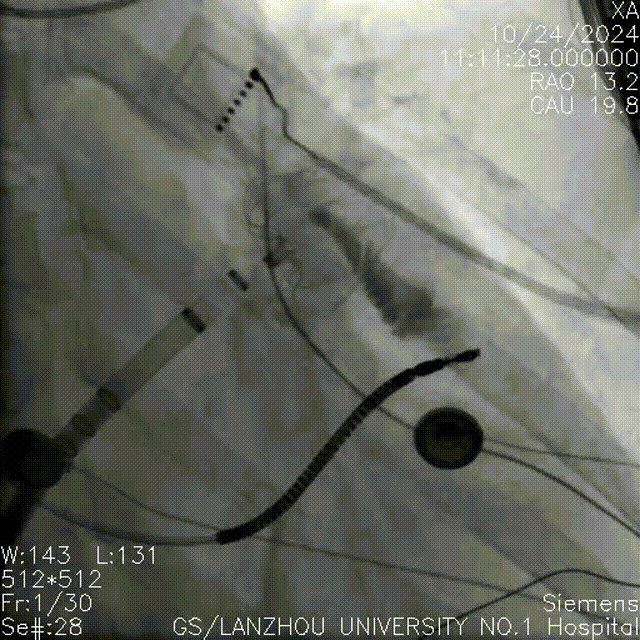

左心耳封堵器完美封堵